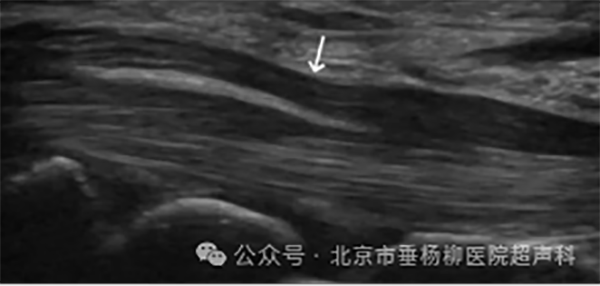

超声引导下肌骨治疗利用超声波成像技术,实时监控和引导治疗器械(如针头)定位到病变部位,进行精准的治疗性操作。超声波能够提供清晰的实时影像,帮助医生精确找到病变组织或部位,确保治疗的准确性和安全性。

超声引导:在超声影像的实时监控下,医生将治疗器械(如注射针头)精确地插入病变部位。超声波提供的实时动态影像,使医生能够清晰地观察到治疗器械的位置和周围的组织结构。